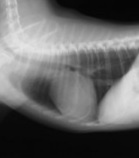

2月10日の心臓検査の診断結果です。

レントゲン検査では、心臓がどんどん大きくなって重度の肥大状態となって気管を圧迫していました。

(正常な心臓)

(肥大した空の心臓)